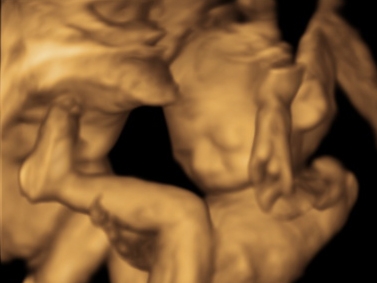

I'm 21 weeks (EDD May 15th) and we have our anatomy scan TODAY!

• @ReesaAnne16 woohoo congrats!!! Love the US!! I'm really hoping I will be getting a 3D US soon!!! Soooo cute!! So thrilled for you!

@ReesaAnne16 yay! So exciting. I love seeing from pictures. Congrats! Can’t wait for some new ones in 2 weeks. Such a long wait.

• @ReesaAnne16 Love the pics!! So adorable :)